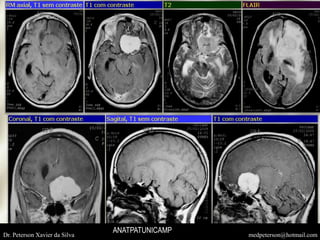

MENINGIOMAS FOSSA MEDIA

MENINGIOMA DE ASA ESFENOIDE

Dr. Peterson Xavier da Silva medpeterson@hotmail.comANATPATUNICAMP

ANATPATUNICAMP